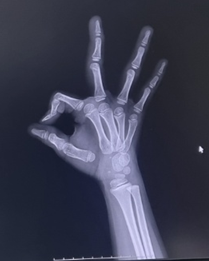

골연령이 몇세 정도 인가요?????

이정도면 골연령이 만으로 몇세정도 인가요?

사진상으로는 정확한 상태를 확인하기는 어려우며 손가락과 손목뼈의 발달 정도와 성장판을 보면 완전하지 않을 수 있고 어디까지나 추측으로 보았을때 10대 후반정도로 보이며 정확한 상태는 병원에 방문하시어 검사 및 상담 가져보시면 좋을 것으로 생각됩니다.

사진상으로 많은걸확인할수는없지만 손가락과 손목뼈의 발달정도와 성장판을보면 완전하지않기때문에 10대후반정도로 보입니다 하지만 실제나이나 성별또는 성장환경에따라서 달라질수있기때문에 본인의 골연령을 확인하기위해서는 병원에서 전문의와상담을받아보는것이 필요할수있습니다

만으로 8세에서 11세 사이로 추측됩니다. 일반적으로 엑스레이 영상촬영을 사용하여 골 연령을 추측하는 방법에는 인종간의 차이나 판독자의 숙련도, 촬영방법에 따라 판독의 오차범위가 존재하므로 정확한 소견은 전문의에게 진료를 받아보시는 방법을 추천드리겠습니다.